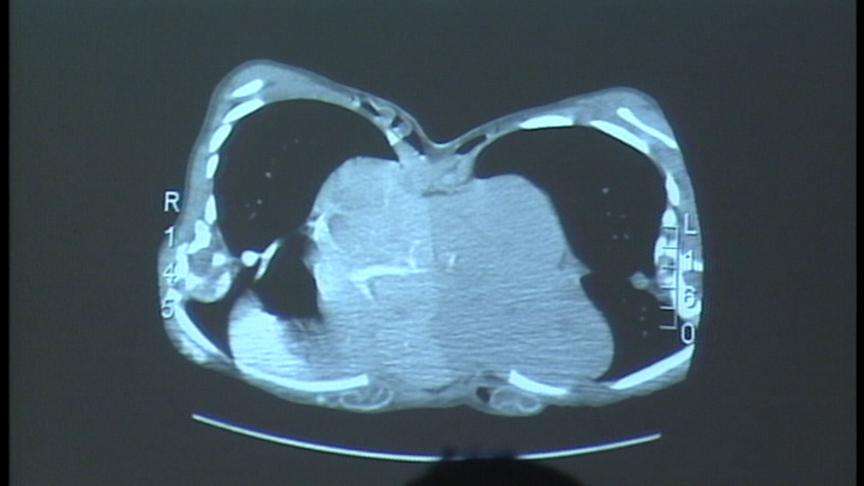

CT scans, x-rays, ultrasounds, blood tests, and more. For the most part, every conceivable picture now outlines what the twins share and what they don't. Kendra and Maliyah are basically two separate girls from the waist up, and one from the waist down. Though they share a pelvis, a fused liver and a single kidney, everybody remains optimistic both will come through this.

While the liver can be split, only one girl will get the kidney. The other will need a transplant, which could place her at greater risk for complications. Surgeons will rebuild the abdominal cavities on both girls by using residual muscle pulled from the legs and a synthetic tissue called Aladerm.

The girls also share the large intestine, which surgeons hope can be split, giving half to one girl and half to the other.